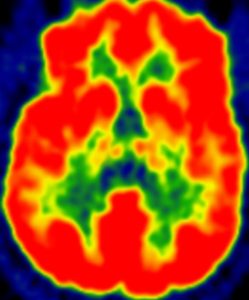

Alzheimer’s disease study links brain health and physical activity

People at risk for Alzheimer’s disease who do more moderate-intensity physical activity, but not light-intensity physical activity, are more likely…

People at risk for Alzheimer’s disease who do more moderate-intensity physical activity, but not light-intensity physical activity, are more likely…